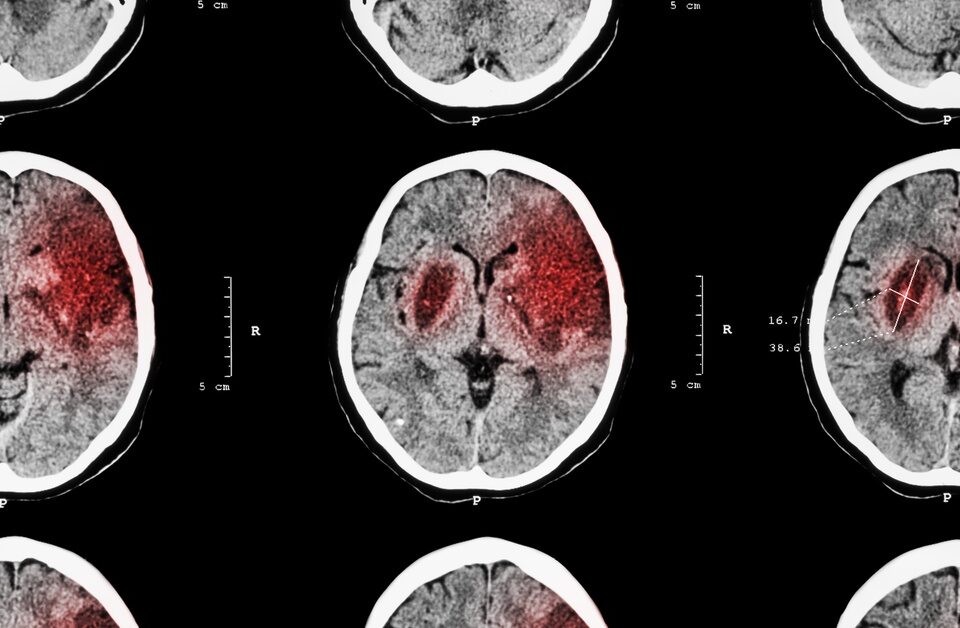

Tissue plasminogen activator, also known as tPA, is a medication commonly given to people who have suffered strokes. What are the risks of this approach?